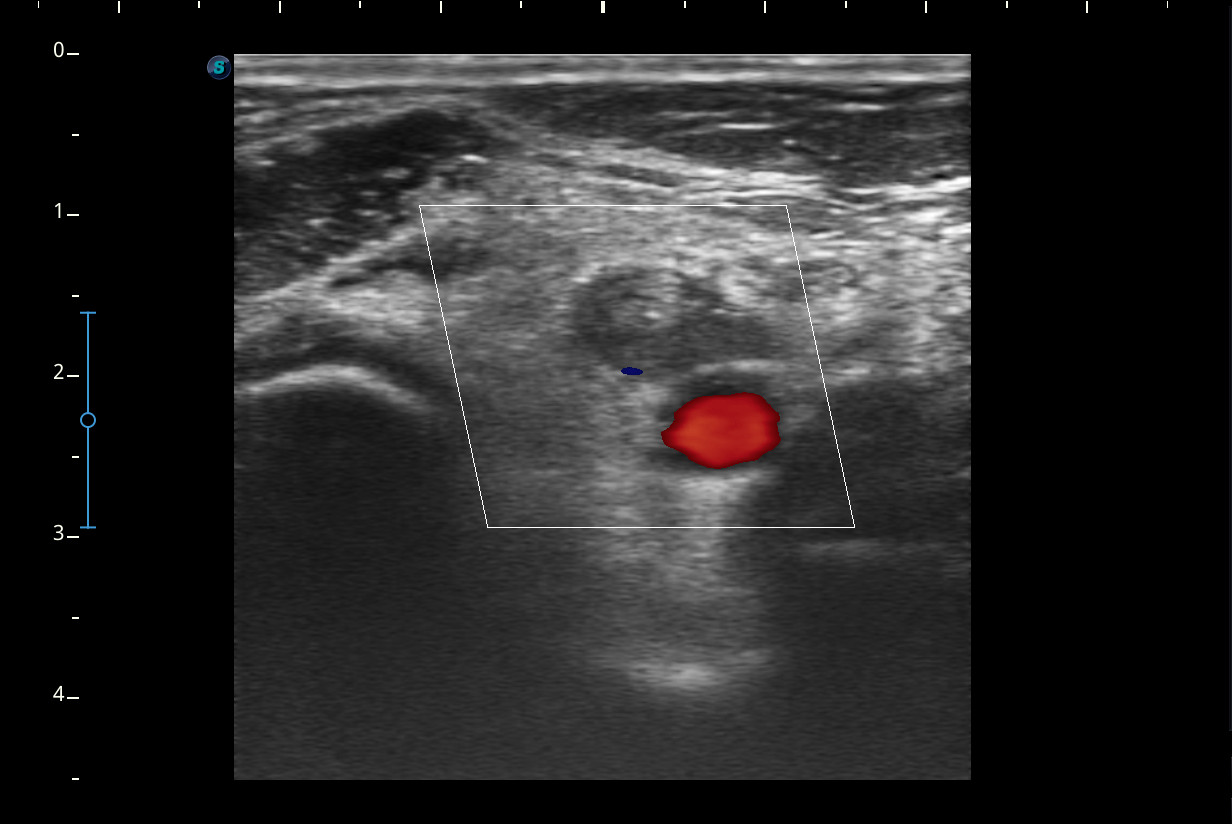

Mujer de 44 años, que presenta desde hace 2-3 semanas dolor e impotencia funcional en la pierna derecha con aumento de volumen y eritema de pantorrilla ipsilateral que en un inicio se trató como rotura fibrilar para la que se pauta reposo y tratamiento analgésico oral. Ha mejorado muy levemente pero persiste dolor en el hueco popliteo e impotencia funcional.Descripción de los hallazgos ecográficos y las imágenes más relevantes para la resolución del caso

A nivel del hueco poplíteo se visualiza presencia de trombosis de la vena poplítea, no así en localizaciones proximales.Otras pruebas complementarias realizadas (si existen)